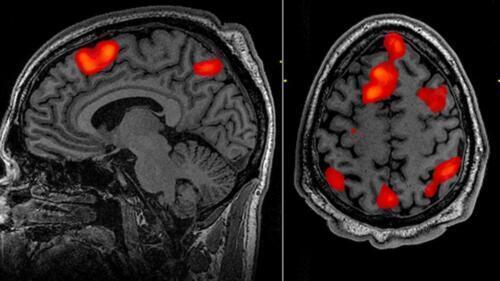

Resonancia magnética funcional (fMRI)

Este tipo de estudio permite identificar:

- Qué áreas del cerebro se activan con un movimiento

- Qué zonas se activan al hablar, escuchar o ver

- Si el paciente está entendiendo un estímulo

Se utiliza mucho en:

- Neurocirugía

- Planificación quirúrgica

- Investigación neurológica avanzada

👉 Estos estudios solo son posibles con equipos de 3 Teslas, debido a la necesidad de máxima señal y precisión funcional.